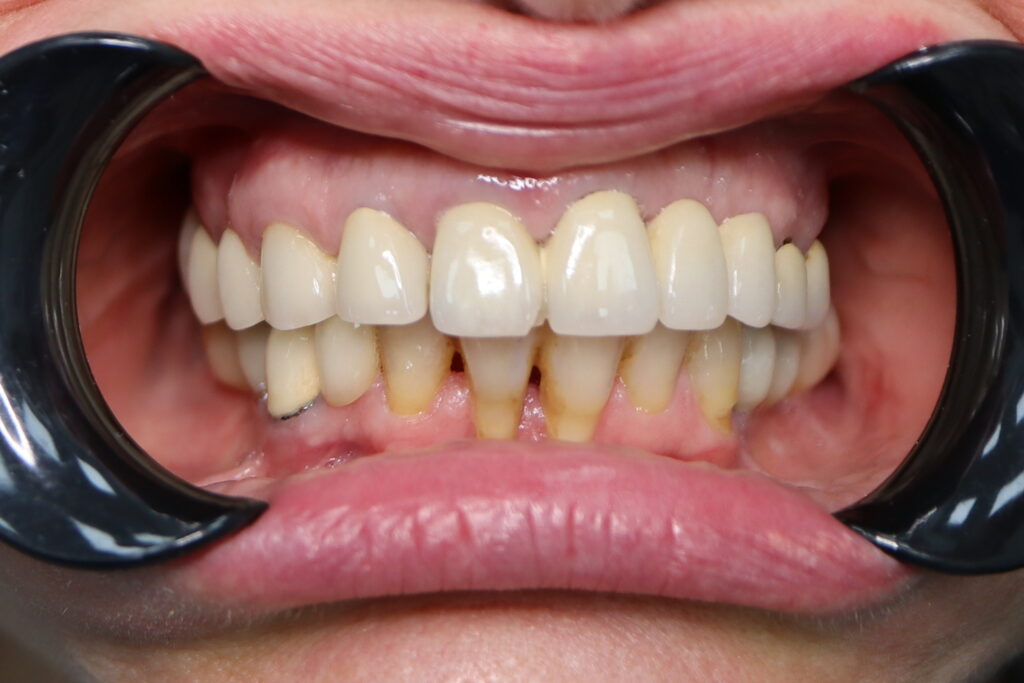

Результаты

Стоимость всего комплекса: 5300 USD (цена указана ориентировочно по курсу НБРБ на день оплаты)

результат имплантации